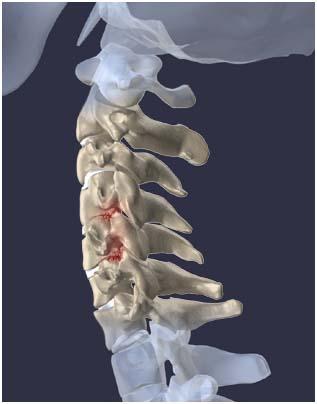

목디스크란?

목을 받쳐주는 뼈를 경추라고 하는데 여기는 뼈가 7개 있고 이 뼈 마디마다 디스크라는것이 있습니다. 이 디스크의 역할은 척추 뼈 사이에 충격을 완화하고 운동할 수 있게합니다. 목디스크는 퇴행성 척추 질환으로 목 주위 근육, 인대가 장기간 압력을 받고 퇴행하여, 디스크가 자신의 역할을 하지 못하고 밀려나고 통증과 같은 목디스크 증상을 보이는 질병입니다. 이 디스크의 위치가 어디에 있는지에 따라 목 이외에도, 손이 저리거나 어깨가 아프고 두통과 같은 다른 목 디스크 증상을 일으킬 수 있습니다. 만약 여러분이 디스크를 그대로 방치하면, 몸이 마비되거나 호흡이 곤란한 상황에 처할 수 있기 때문에 여러분의 관심을 필요로 할 것입니다.